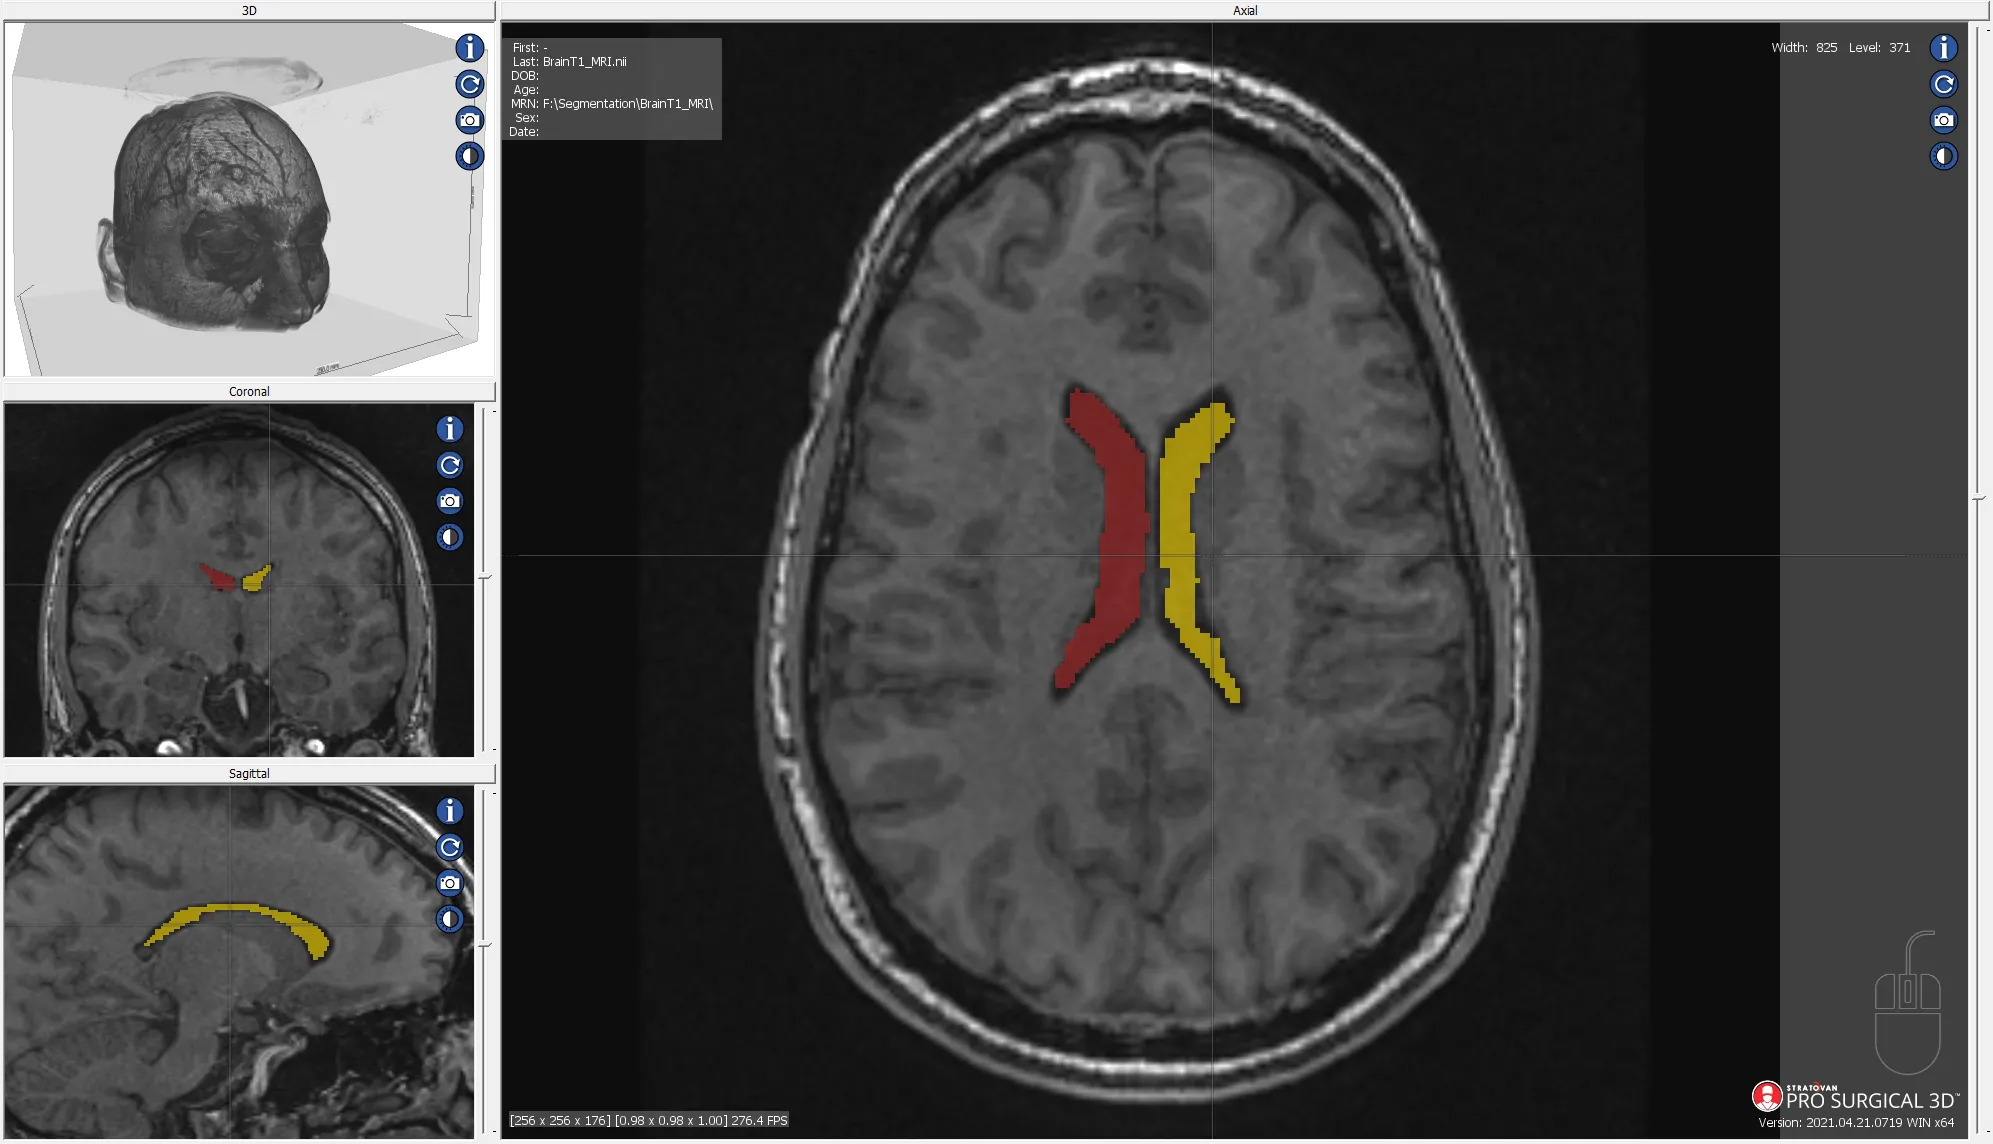

MRI segmentation of human brain ventricle

Quality assurance review of the AMOS 2022 Grand Challenge data